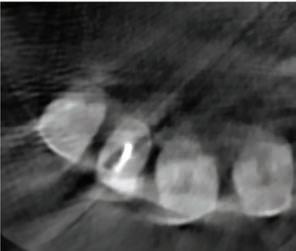

A 30-year-old patient, with a negative medical history, came to the clinic requesting the replacement of the previous composite reconstruction performed 10 years earlier following a trauma to UR1.

On clinical examination, UR1 was responsive to viability testing, and did not present periapical lesions on the radiograph performed on the same day (Figure 1). UR1 was discoloured and in a more palatal position than the contralateral central UL1 (Figure 2). The aesthetic analysis highlighted an asymmetry of the gingival zenith between UR1 and UL1. Through the use of a periodontal probe, after plexus anaesthesia, the altered passive eruption of the type IA junctional epithelium was confirmed according to the classification of Coslet et al. (Figure 3).

FIGURE 1: Radiograph without periapical lesion.